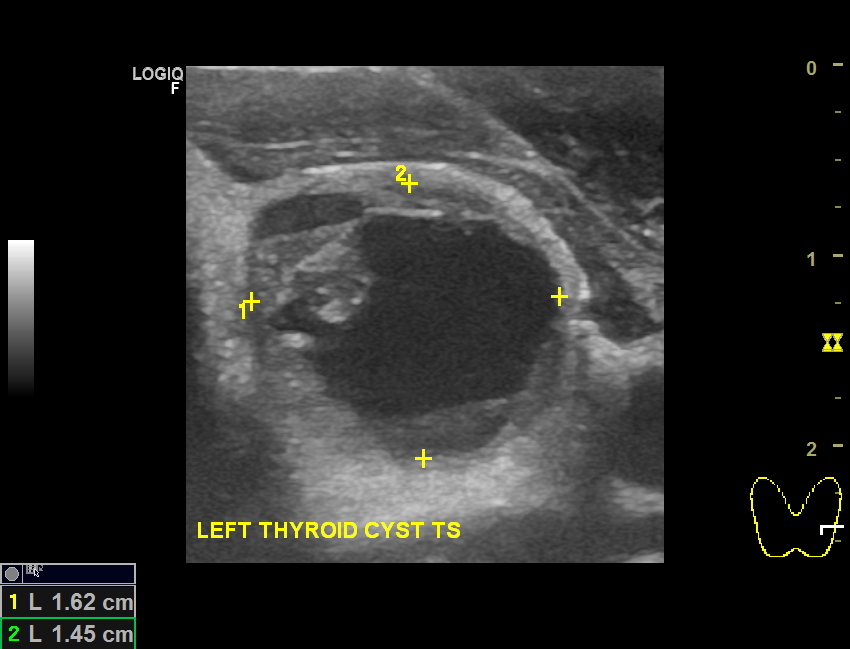

Colloid cyst of thyroid Image